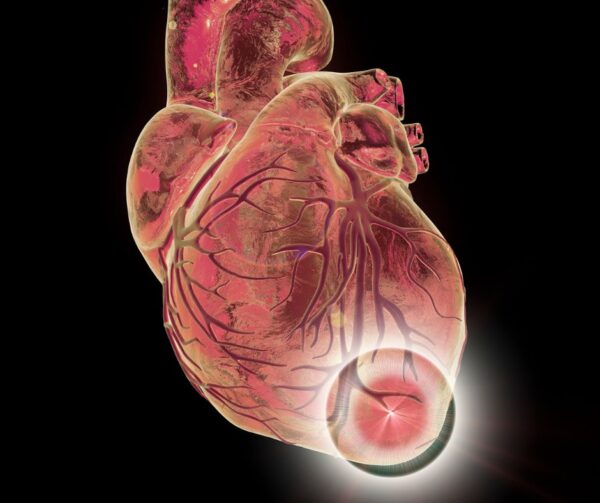

Un aneurisma del ventrículo izquierdo se define como una área de cicatriz miocárdica que presenta una forma bien delimitada y que, durante la sístole, experimenta un abultamiento inusual, lo que…